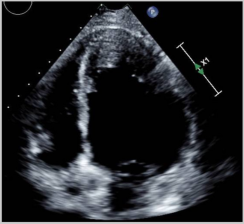

| Imaging Modality | Imaging Illustrations | Description |

|---|---|---|

| Echocardiography | ![]() | Mild left-ventricular dilation and systolic dysfunction |